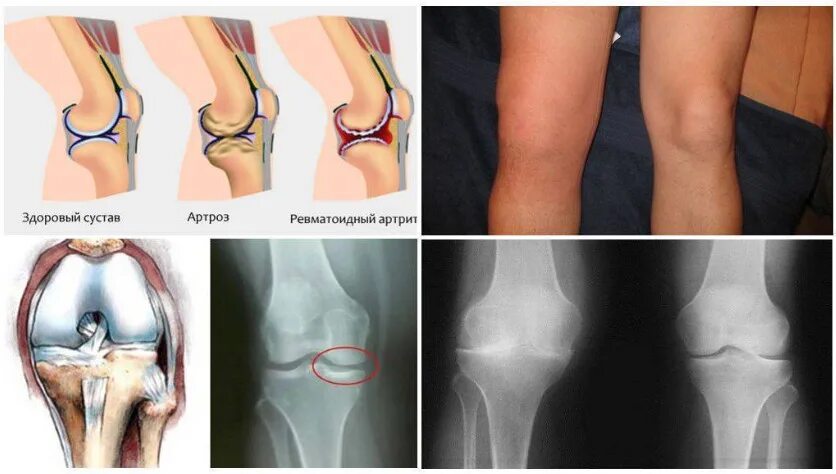

Гонартроз мрт